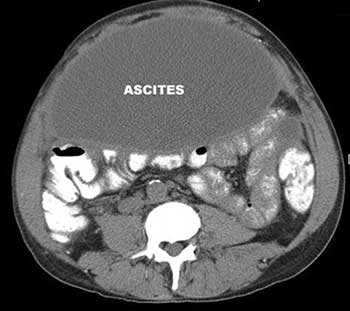

Минимальный по объёму асцит выявляют только при инструментальном исследовании - УЗИ или КТ брюшной полости. Умеренный асцит, начиная с объёма жидкости более литра-полутора, врач определит при обычном осмотре. УЗИ брюшной полости позволит определить объём экссудата.

Если в брюшной полости скапливается небольшое количество жидкости (100-400 мл), симптомы отсутствуют. В таких случаях асцит обнаруживают зачастую случайно во время УЗИ или КТ органов брюшной полости.

Внешние признаки асцита становятся хорошо заметны, когда количество жидкости в брюшной полости достигает 0,5-1 литра. Живот при этом заметно увеличен. Когда пациент стоит, он выглядит отвисшим, в положении лежа — распластан, боковые его части выступают. Врачи называют такую картину образно «животом лягушки».

- УЗИ, КТ и МРТ помогают диагностировать асцит и оценить количество жидкости в брюшной полости, состояние внутренних органов, обнаружить злокачественную опухоль, оценить количество, размеры, локализацию патологических очагов, степень прорастания опухоли в различные органы и ткани;

Асцит - это вторичное состояние, характеризующееся накоплением экссудата или транссудата в свободной брюшной полости. Клинически проявляется увеличением объема живота, тяжестью, чувством распирания и болями в брюшной полости, одышкой. Диагностика асцита включает проведение УЗИ, КТ, УЗДГ, диагностической лапароскопии с исследованием асцитической жидкости. Для патогенетического лечения необходимо установить причину, вызвавшую скопление жидкости; к симптоматическим мероприятиям при асците относятся назначение мочегонных средств, пункционное удаление жидкости из брюшной полости.

В ходе осмотра гастроэнтеролога исключаются другие возможные причины увеличения объема живота - ожирение, киста яичника, беременность, опухоли брюшной полости и т. д. Для диагностики асцита и его причин проводится перкуссия и пальпация живота, УЗИ брюшной полости, УЗДГ венозных и лимфатических сосудов, МСКТ брюшной полости, сцинтиграфия печени, диагностическая лапароскопия, исследование асцитической жидкости.

Перкуссия живота при асците характеризуется притуплением звука, смещением границы тупости при изменениях положения тела. Прикладывание ладони к боковой поверхности живота позволяет ощутить толчки (симптом флюктуации) при постукивании пальцами по противоположной стенке живота. Обзорная рентгенография брюшной полости позволяет идентифицировать асцит при объеме свободной жидкости более 0,5 л.